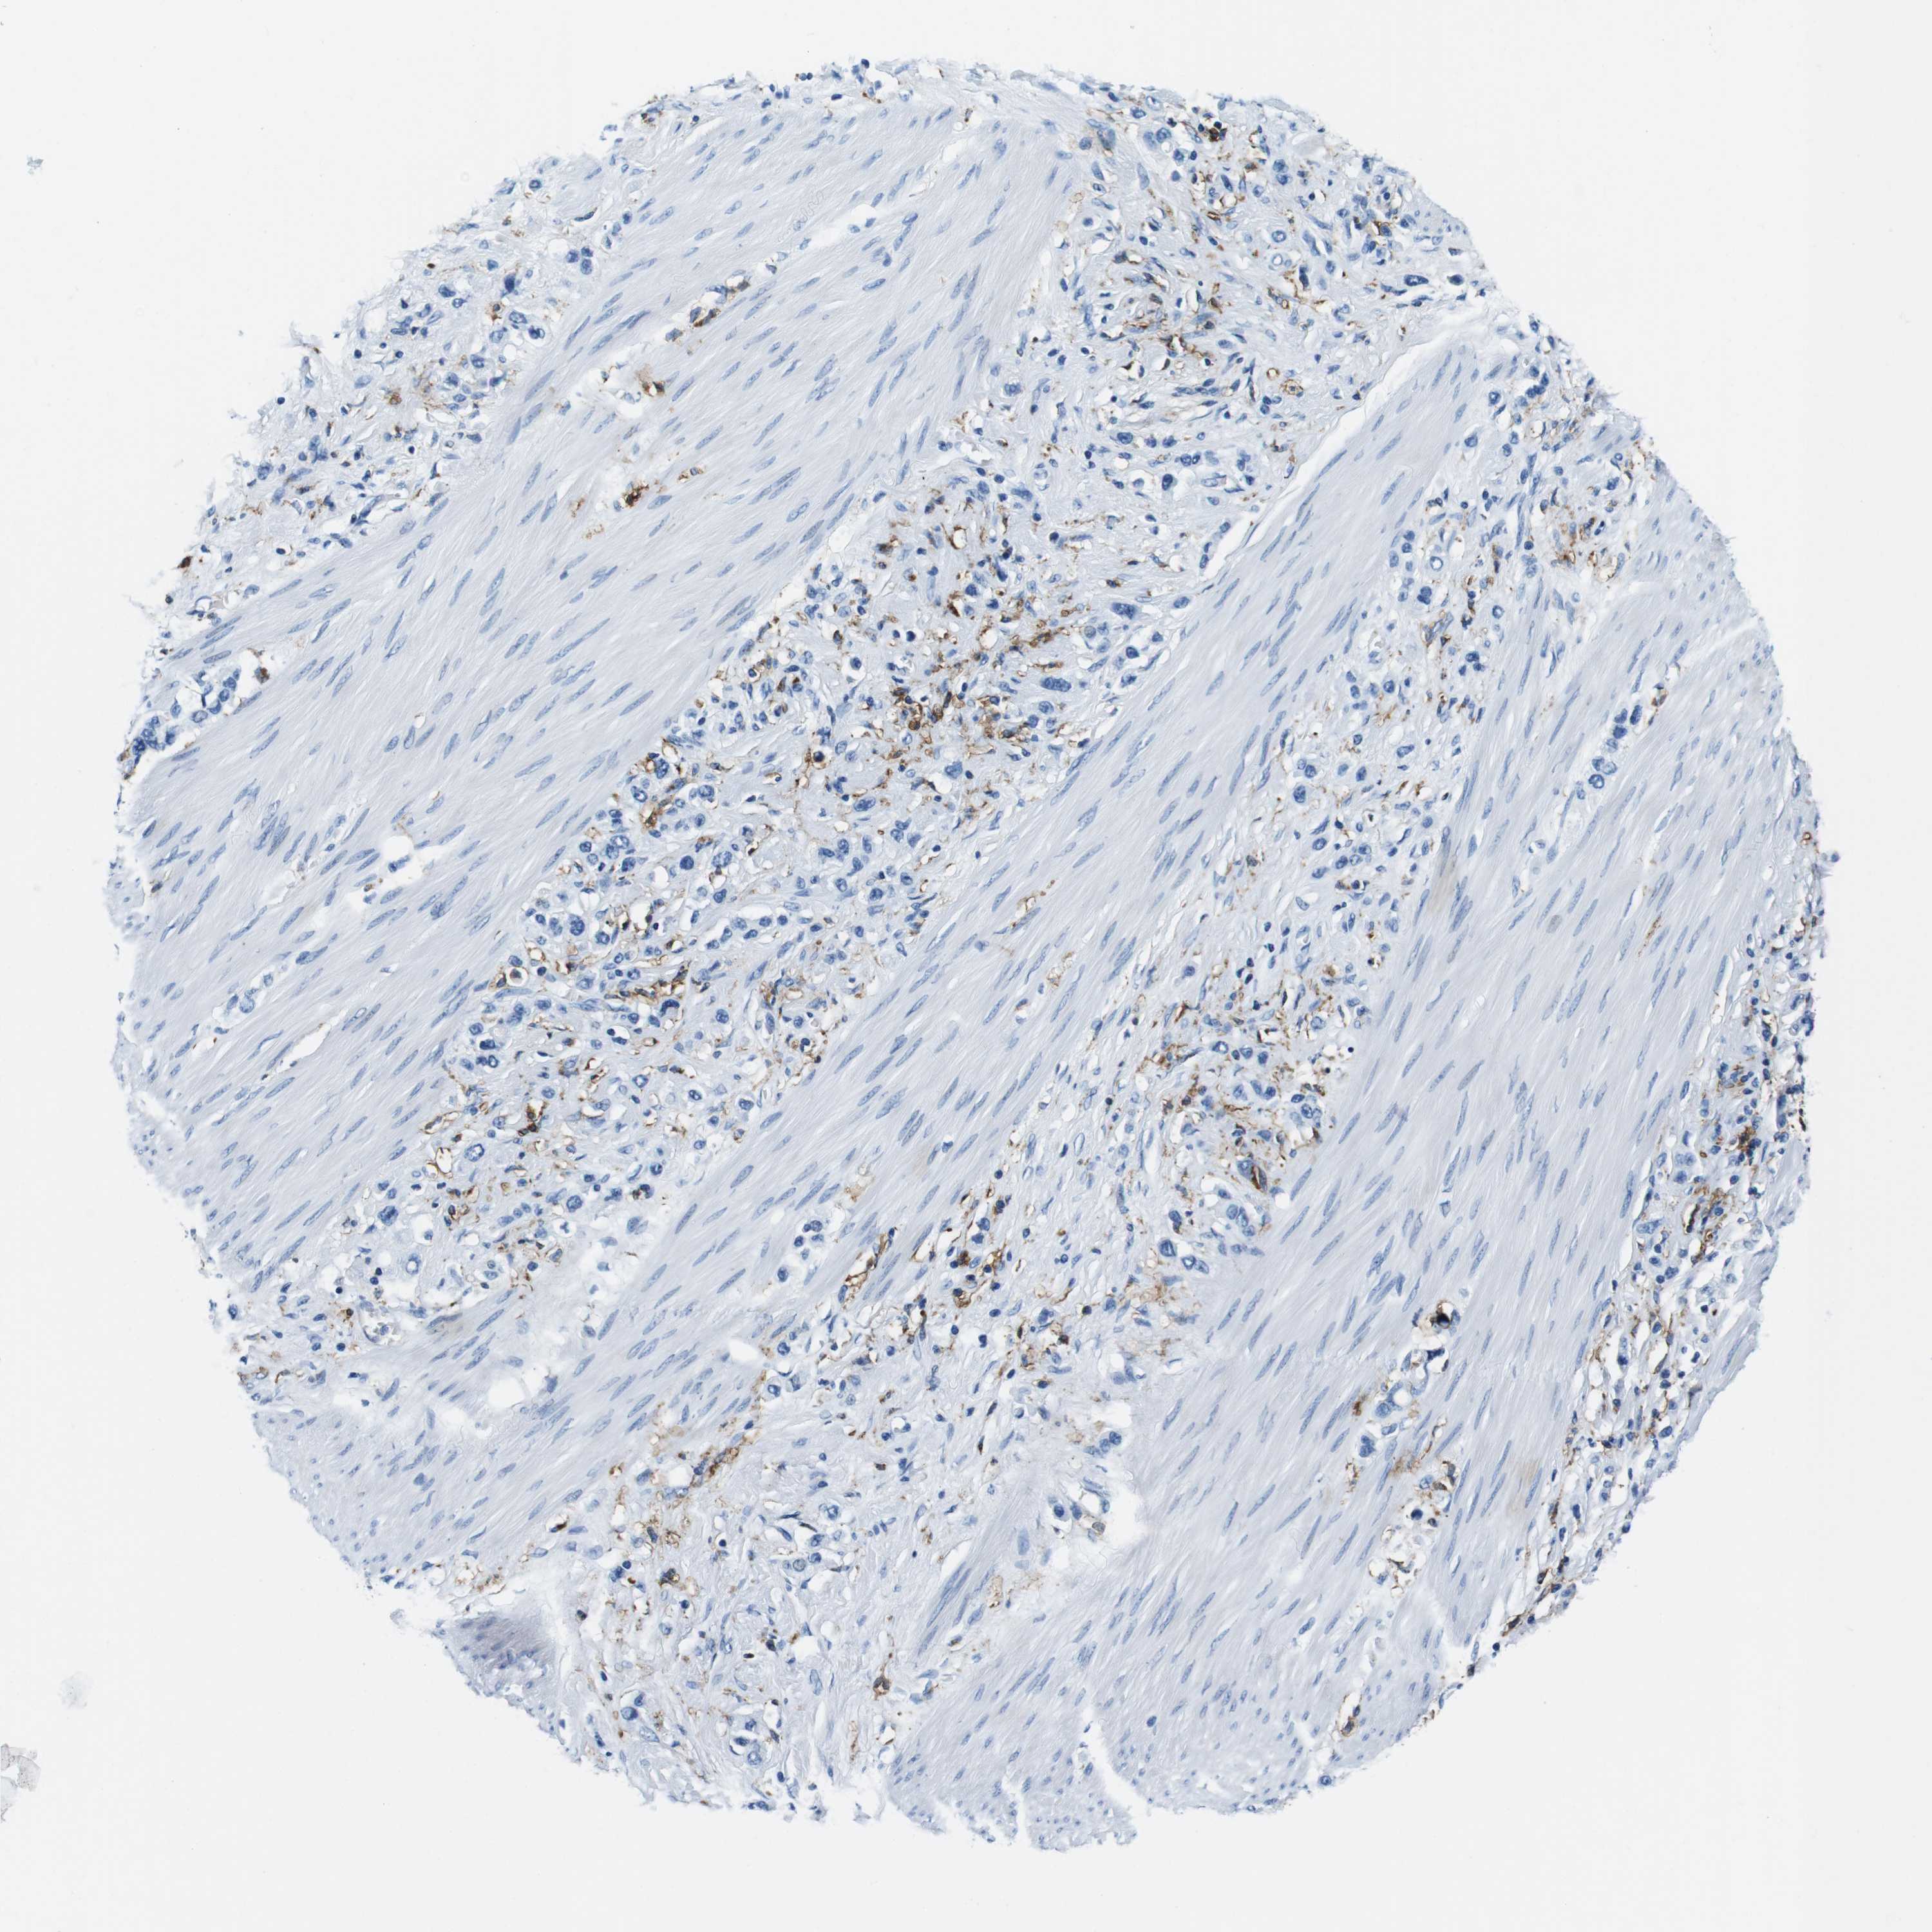

STOMACH CANCER - Protein expressioni

A mouse-over function shows sample information and annotation data. Click on an image to view it in a full screen mode. Samples can be filtered based on level of antibody staining by selecting one or several of the following categories: high, medium, low and not detected. The assay and annotation is described here.

Note that samples used for immunohistochemistry by the Human Protein Atlas do not correspond to samples in the TCGA dataset.

Antibody stainingi

Antibody staining in the annotated cell types in the current human tissue is reported as not detected, low, medium, or high, based on conventional immunohistochemistry profiling in selected tissues. This score is based on the combination of the staining intensity and fraction of stained cells.

Each image is clickable and will lead to virtual microscopy that enables deeper exploration of all samples and also displays staining intensity scores, fraction scores and subcellular localization as well as patient and tissue information for each sample.

Antibody HPA043151

Antibody CAB015400

Antibody CAB034021

Staining

High

Medium

Low

Not detected

Intensity

Strong

Moderate

Weak

Negative

Quantity

>75%

75%-25%

<25%

None

Location

Nuclear

Cytoplasmic/membranous

Cytoplasmic/membranous,nuclear

Adenocarcinoma, NOS